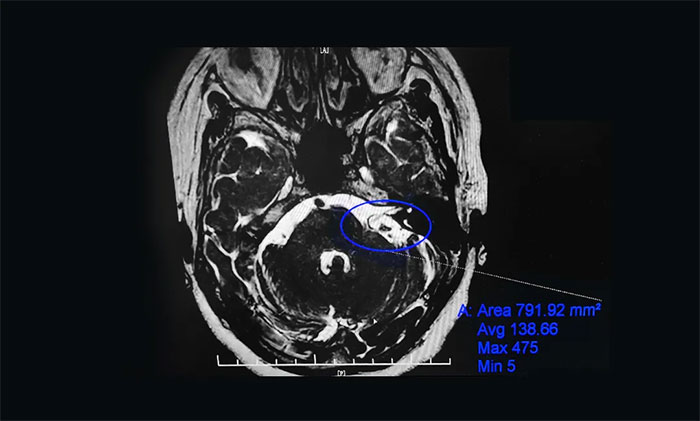

為進(jìn)一步治療,劉阿姨在家人陪伴下慕名求醫(yī)上海藍(lán)十字腦科醫(yī)院。入院后,楊忠旭教授團(tuán)隊(duì)認(rèn)真評(píng)估了劉阿姨面肌痙攣發(fā)生的頻率、強(qiáng)度和持續(xù)時(shí)間,并完善了核磁顱神經(jīng)檢查。面神經(jīng)MRTA+增強(qiáng)顯示:左側(cè)面神經(jīng)與周圍小血管關(guān)系密切。

▲患者左側(cè)面神經(jīng)與周圍小血管關(guān)系密切

術(shù)中,在顯微鏡下見(jiàn)基底動(dòng)脈走形迂曲并騎跨左側(cè)面神經(jīng)。在電生理監(jiān)測(cè)“保駕護(hù)航”下,楊忠旭教授用特制的器械分離壓迫面神經(jīng)根部的血管,然后放入特制的墊棉將血管與神經(jīng)隔離開(kāi)來(lái),解除血管對(duì)面神經(jīng)的壓迫。整個(gè)手術(shù)過(guò)程出血少,時(shí)程短,術(shù)后劉阿姨面部肌肉再也沒(méi)有抽搐,整個(gè)人的精神面貌煥然一新,目前已經(jīng)康復(fù)出院。